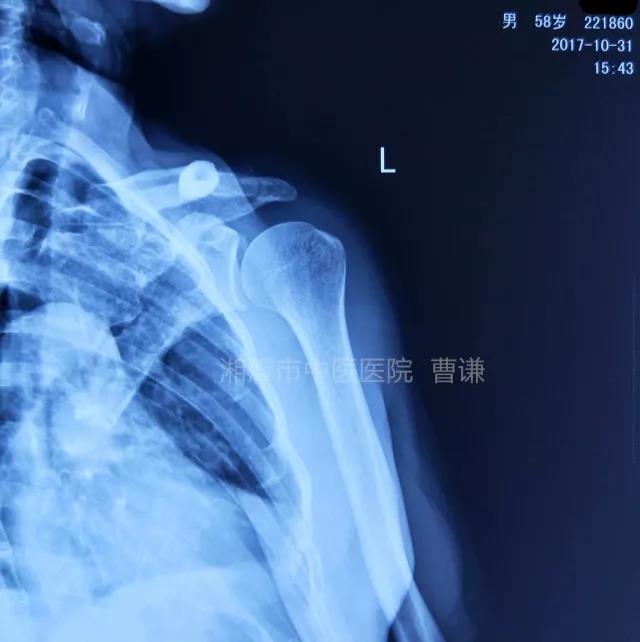

就诊我院后完善CT,诊断明确——左肩关节后脱位:

予以手法复位后拍片复查显示“灯泡征”消失,复位成功。讨论:肩关节后脱位在临床较为少见,特别是影像科经验不足很容易漏报,所以我们临床医生一定要自己仔细阅片,同时要结合体查来进行诊断,防止漏诊。肩关节后脱位时体查也有明显特征:肩关节前方明显变平,喙突较平时明显凸起容易触及,而肩关节后方明显丰满,上臂一般处于内旋内收位,无法主动外旋外展。肩关节后脱位的手法复位相对于前脱位的复位来说也比较容易。患者一般可以取坐位,助手自患侧腋下环抱患者稳定患者躯体,术者一手拉患肢上臂稍牵引内旋,一手自后方推顶肱骨头一般可以复位,如果单纯推顶无法复位也可以术者两手握住伤肢缓慢外展并沿肱骨纵轴牵引,然后逐渐外旋上臂即可复位。整复完成后可以把持患肢作肩关节各个方向的小幅度被动活动,防止肩关节粘连,肩关节后脱位的固定方法与肩关节前脱位的固定方法不同,应将患肢置于上臂外展、后伸、外旋位固定,即外展30度、后伸30度和轻度外旋位,用外展支架固定3周后,循序渐进开始肩关节功能康复。